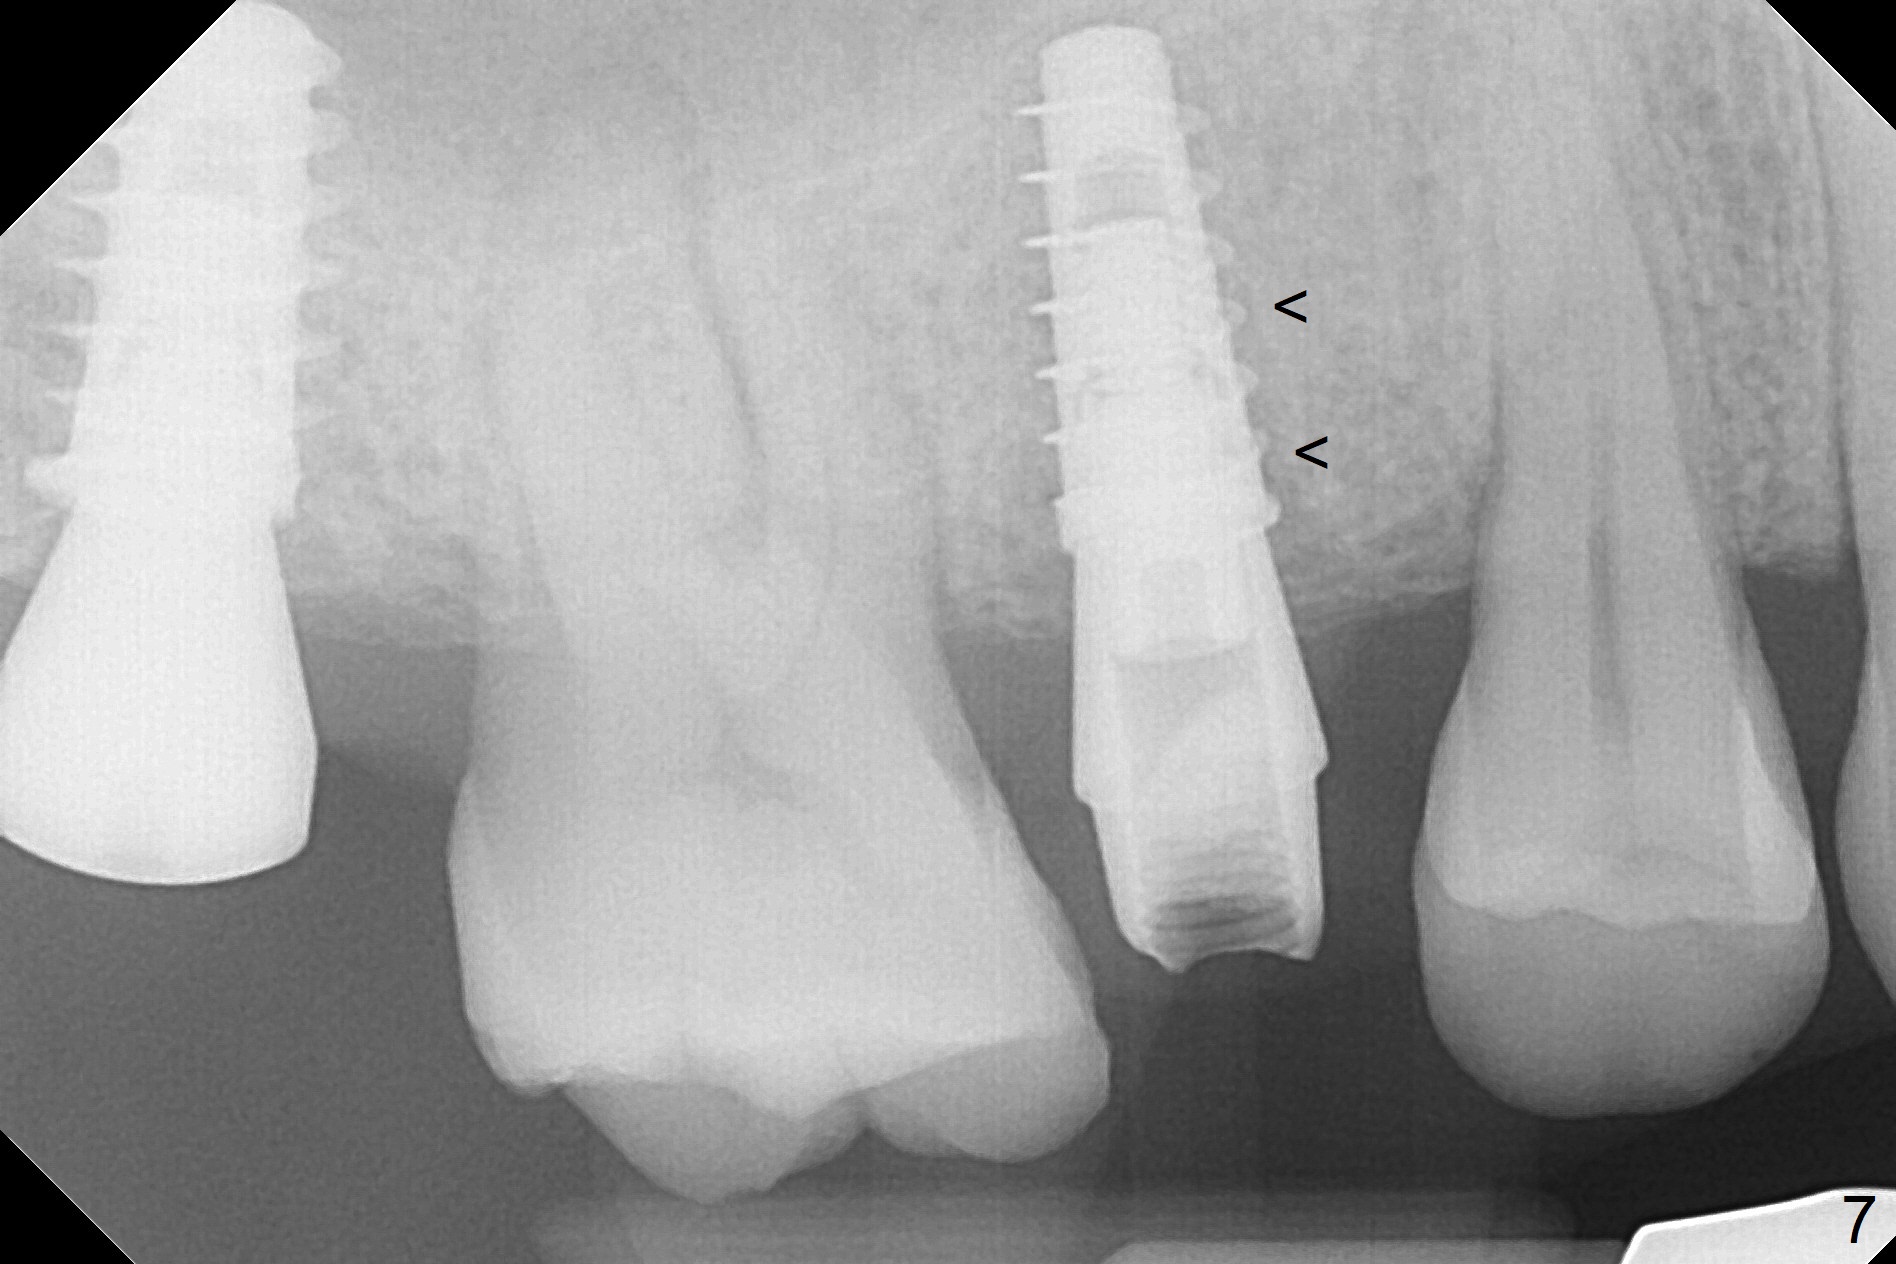

A 47-year-old man returns emergently with subgingival fracture of the lingual (L) cusp of the tooth #4 (Fig.1-3). After extraction (no bony defect) without drilling, a 4x11 mm dummy implant is placed as a tap drill with satisfactory stability (Fig.4,5). To get subcrestal placement, a shorter (4x9 mm) implant is inserted with insertion torque of < 35 Ncm. In retrospect, a larger implant (4.5 mm) would be better in term of primary stability. After allograft placement into the buccal and lingual gaps, a 4.5x4(4) mm abutment is placed for an immediate provisional. There is a peri-implant gap 7 months postop (Fig.7<, as compared to the implant at #2 (6 months postop)) . When the loose abutment is being retightened, the patient feels pain, although the gingiva appears healthy (Fig.8). A larger implant should have been used; the abutment should have been removed. The implant dislodges while the abutment is untightened 8 months postop. The osteotomy is found intact. A 4.5x11 mm dummy implant is placed 2 mm subgingival with 20 Ncm (Fig.9). When a 4.5x11 mm definitive implant is placed 3 mm subgingival (Fig.10,11), torque reaches 50 Ncm. A 5.5x3 mm healing abutment is placed. Three months postop, the implant is stable (Fig.12,13) and impression is taken.